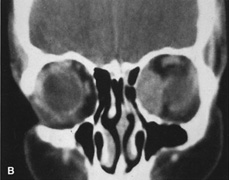

Fig. 14. A,B. Large intraorbital lymphangioma causing proptosis and optic nerve compression in a 2-year-old child. C. View of the left orbit from above after removal of the frontal bone flap, including the supraorbital rim and orbital roof. An extensive exposure of the entire superior and lateral orbit is afforded. The levator and superior rectus complex is being retracted laterally with a muscle hook, whereas the Freer elevator retracts the superior oblique muscle medially. The frontal nerve can be seen running from posterior to anterior over the superior orbit. The orbital mass is exposed in this fashion. D. The fronto-orbital bone flap is wired back in place after completion of the procedure. E. Postoperative appearance of the patient. F. The postoperative CT scan shows complete removal of the lymphangioma. This large and diffuse lesion would have been difficult to remove with any other approach.